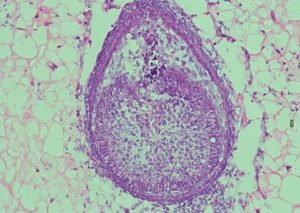

Оваа средина, која научниците ја нарекуваат “скеле”, е клучот за успех. Во последната студија, наместо колагенот кој се користел во 2013 година, тимот сега користи хидрогел, полимер со висока содржина на вода. “Прво, ние собираме клетки од ембриони на глушец, потоа ги мешаме и ги центрифугираме за да добиеме мала клеточна топка. Потоа го инјектираме тоа зрно во хидрогелот и го растеме околу осум дена”, објасни Ксуечен Жанг, докторант на Кралскиот колеџ и коавтор на истражувањето. По осум дена, во внатрешноста на хидрогелот се формираат структури во вид на заб. Во претходната студија, таквите “забни ембриони” биле пренесени на глушец, каде што тие се развиле во забна структура со корени и глеѓ.